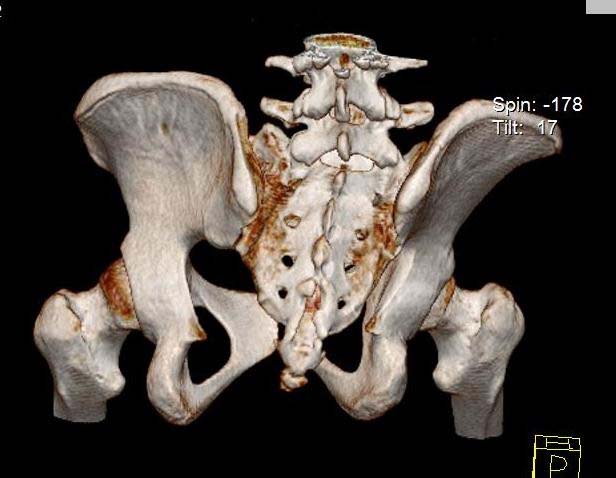

Здравствуйте.Помогите с диагнозом и тактикой лечения.

Больная 15 лет. Жалобы: на укорочение правой нижней конечности, хромоту. Анамнез: Со слов

болеет с детства, травму отрицает. Ранее за медицинской помощью не обращалась. Последние 2

года отмечает резкое укорочение конечности. Локально: При осмотре отмечается умеренное

искривление позвоночника во фронтальной плоскости, умеренная асимметрия лопаток и

надплечий. Скошенность таза. Отмечается укорочение правой нижней конечности на 3 см.

Движения в тазобедренном и коленном суставах в полном объеме. Нейрососудистых нарушений в

периферических отделах нет.